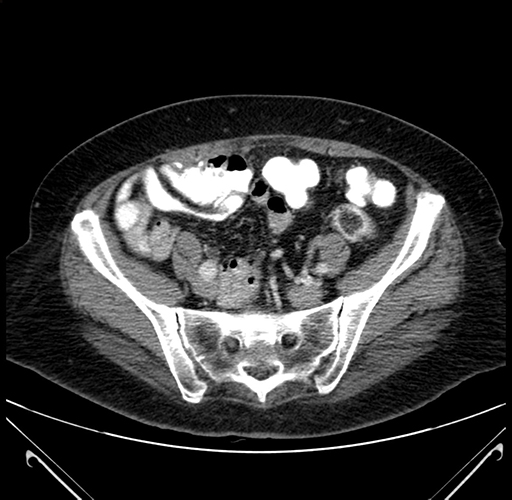

Coronal Venous